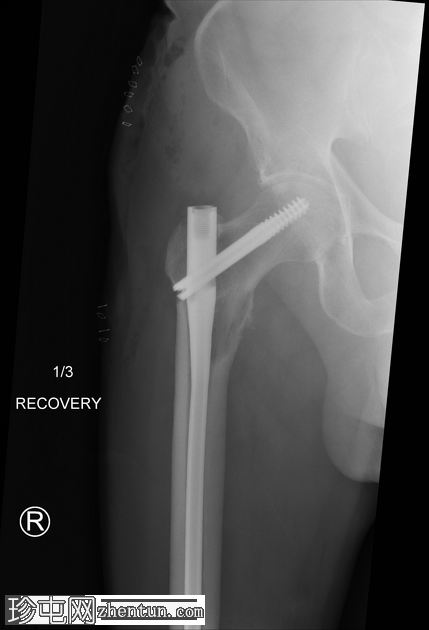

作者:大江 | 时间:2025-10-8 17:00:06 | 阅读:209| 显示全部楼层

跌倒后右腿缩短且外旋。既往股骨内固定术。已知甲状腺癌伴骨转移。

跌倒后右髋关节缩短且外旋。

右侧髓内钉近端骨折(位于拉力螺钉孔位)。

空心髋螺钉组件完好。

股骨转子间骨折延伸至股骨近端转移灶,小转子粉碎。

这是股骨髓内钉断裂的典型案例。由于担心股骨近端溶骨性病变以及患者存在病理性骨折的风险,因此置入了髓内钉。髓内钉断裂是一种罕见但严重的并发症。

在本例中,髓内钉断裂发生在拉力螺钉孔(穿过股骨颈的螺钉)的水平,该水平可能是髓内钉本身较薄弱的部位。靠近该水平的溶骨性病变可能导致了不稳定性和髓内钉的异常应力。